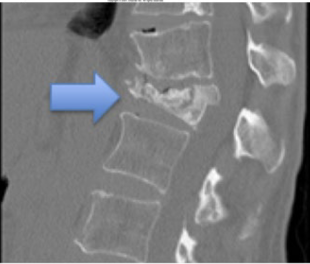

What type of fracture is this?

Compression

What is a compression fracture?

Vertebral fracture displays as decreased vertical dimension of anterior vertebral body

Lower t-spine usually